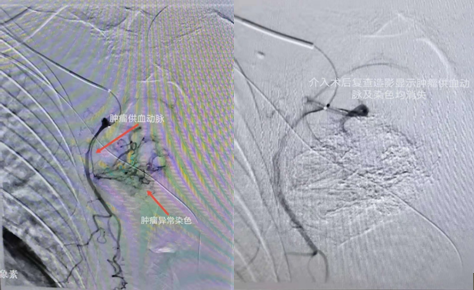

介入術(shù)中圖片

近日,吉林國文醫(yī)院淋巴瘤科與介入一科相互合作,成功為一例皮膚惡性黑色素瘤患者,實施了實體腫瘤動脈灌注化療栓塞術(shù),患者李某某10個月前曾確診為皮膚惡性黑色素瘤,腫瘤分布在左側(cè)腋下,患者既往曾多次行靜脈化療及免疫治療,但腫瘤病情仍然繼續(xù)進(jìn)展,患者目前左側(cè)腋下腫瘤病灶增長較快,伴有局部脹痛感,淋巴瘤科左淑波主任綜合分析患者病情后,邀請介入一科韓長清主任進(jìn)行共同商討治療方案,評估是否可行介入手術(shù)治療,經(jīng)兩位主任共同商討后決定,可給予患者行腫瘤供血動脈化療栓塞術(shù)介入治療。介入術(shù)中非常順利,成功尋找到腫瘤供血動脈并給予治療,術(shù)后患者恢復(fù)良好,疼痛癥狀有所改善。